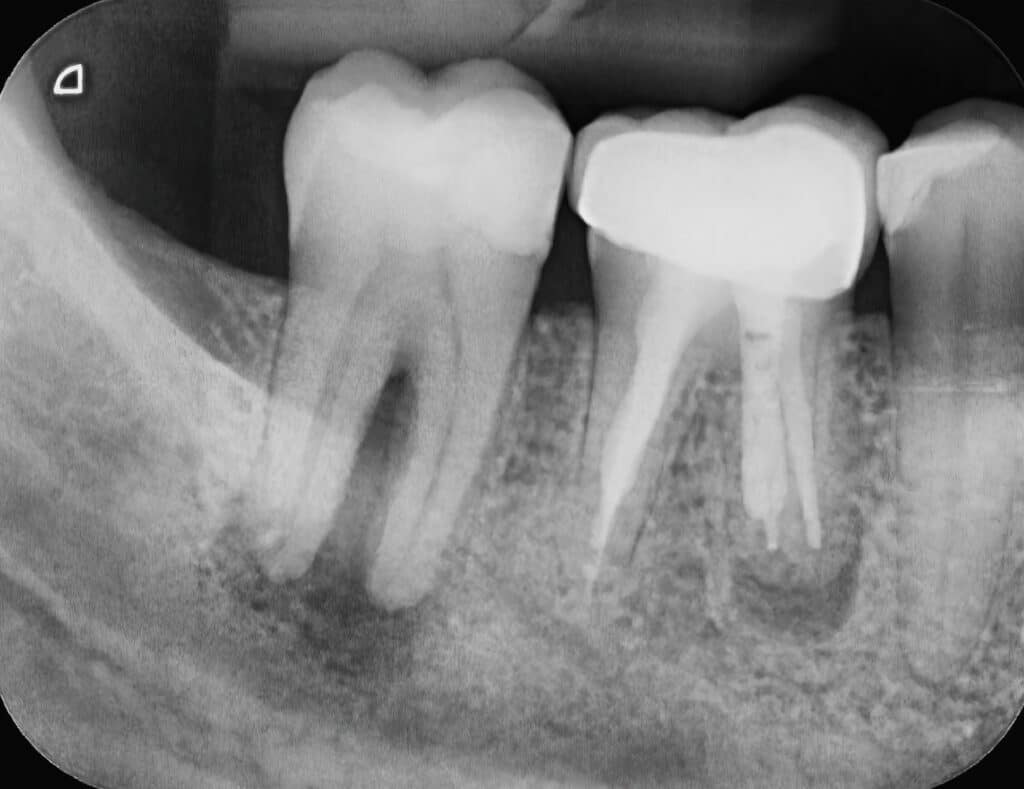

X-ray Of Two Human Tooth Molars